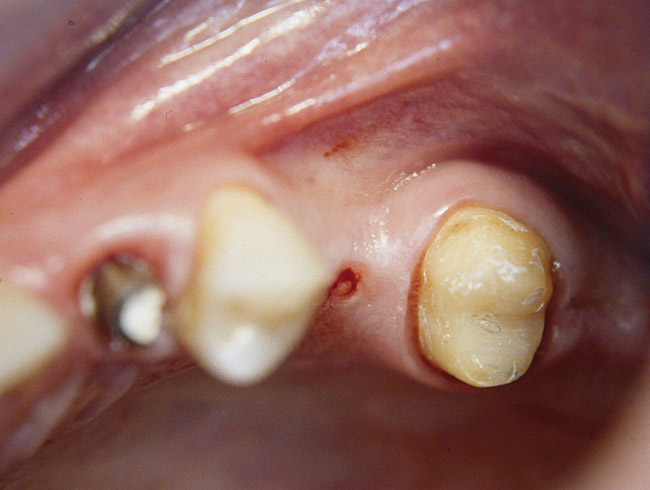

Second-stage surgery was performed after 4 months (Figure 8); healing abutments were placed and the soft tissue was allowed to heal for 5 more weeks. Then, splinted porcelain-fused-metal (PFM) crowns supported by custom gold abutments were delivered (Figure 9 and Figure 10).

Figure 9  Final implant-supported PFM restorations.

Figure 9

Figure 10  Posttreatment radiograph, after cementation of the final restorations.

Figure 10